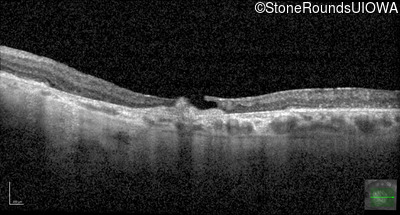

Optical Coherence Tomography - Right - 20/100

Exemplar / OCT Stack